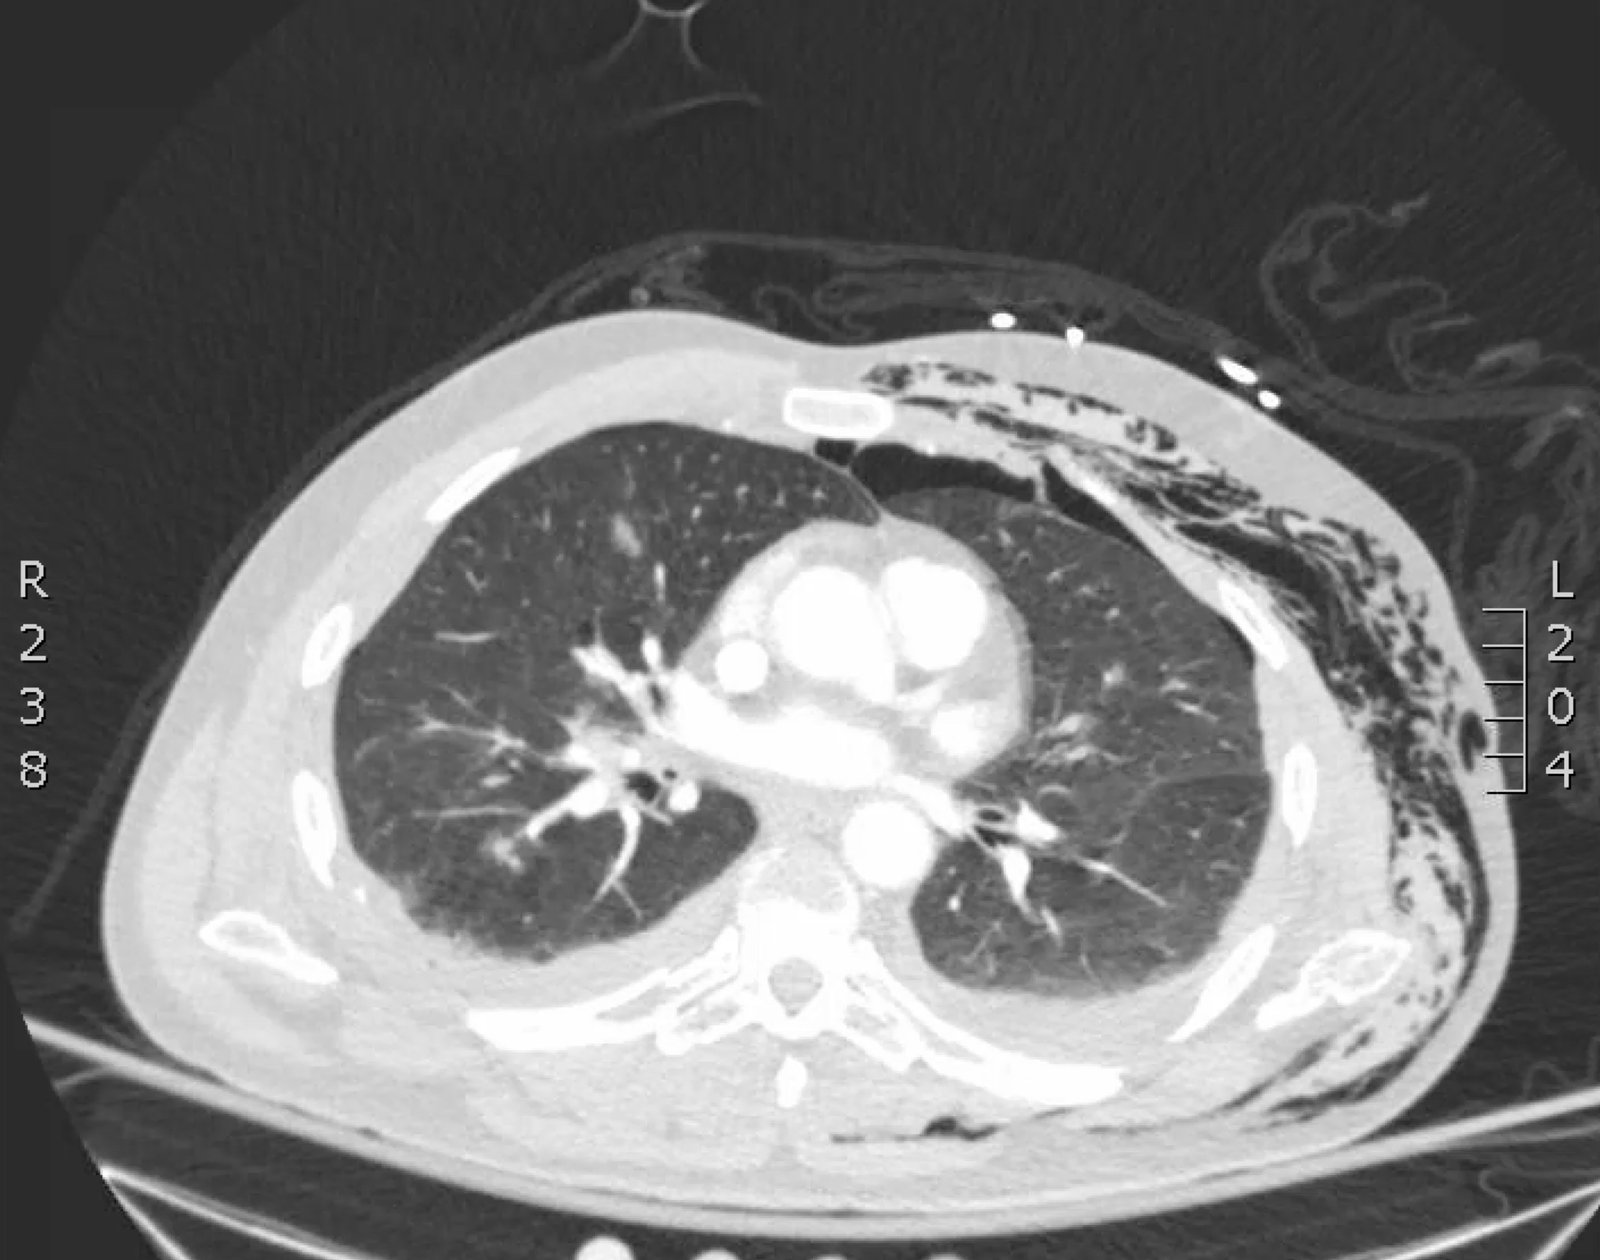

Plain film anteroposterior (AP) radiography of the chest shows left-sided subcutaneous emphysema (red arrow) with overlapping muscle striations of the pectoralis major (green arrow). After chest tube placement (blue arrow), AP chest radiography shows persistent left-sided subcutaneous emphysema (red arrow). CT of the chest shows pneumomediastinum (blue arrow), left apical pneumothorax (pink arrow), and subcutaneous emphysema (red arrow) at the level of T2. At the level of T6, rib fractures can be visualized on the CT (yellow arrow). At the level of T8, left sided pneumothorax is also seen (pink arrow) as the absence of lung tissue on CT.

Injuries of the thorax account for 25% of all mortality in trauma patients, of which many are preventable deaths by simple interventions.1,2 One sign commonly seen in patients with chest trauma is subcutaneous emphysema. The presence of this underlying emphysema has been suggested to be a sign of injury to the respiratory tract, making it clinically significant.3,4 Specifically, subcutaneous emphysema has been shown to be a clinical predictor of occult pneumothorax, with an odds ratio of 5.47.3 Furthermore, these injuries to the respiratory tract (pneumothorax /hemothorax, pneumomediastinum, etc.) can lead to hemodynamic instability and respiratory failure.4-6

In this patient, given the findings of multiple bilateral rib fractures, bilateral hemothorax/pneumothorax and multiple spine fractures, bilateral chest tubes were placed which had immediate output. The patient was admitted to surgical intensive care unit for chest tube management, pulmonary hygiene and further management of his other injuries.